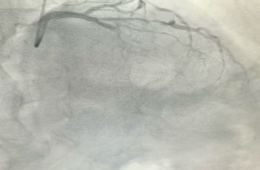

微创介入精准施治日照市康复医院近日,日照市康复医院心脏康复科团队成功为一名近70岁老年冠心病患者实施了冠脉支架植入术,精准在前降支(LAD)病变处植入支架一枚,解决了其长达6年的胸闷、憋气等症状,使患...